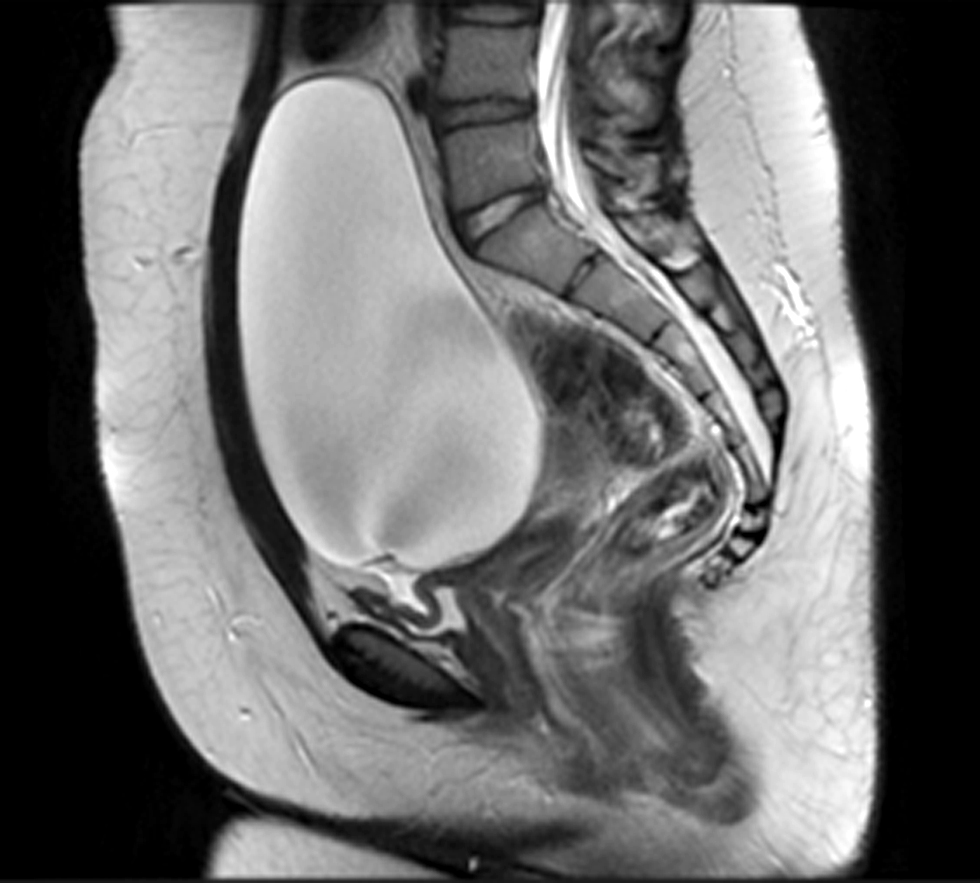

Figure 2 – A simple, well delimited ovarian cyst, measuring 175 x 80 mm, compressing the bladder, with no locoregional criteria of malignancy

One year after total thyroidectomy, the patient complained of hypogastric discomfort and low vesical compliance, with increasing levels of urinary creatinine. Her TSH levels had increased again to >100000 UI/mL. A simple left ovarian cyst with 174 x 80 mm compressing the bladder was identified in abdominal-pelvic ultrasound (fig. 1). Magnetic resonance confirmed the presence of an OC (175 x 140 x 100 mm) in the left ovary and the absence of loco-regional aggressiveness findings (fig. 2). She had normal levels of FSH and LH, non-elevated testosterone or oestradiol levels and normal serum levels of beta-hCG, alpha-fetoprotein and CA-125. The patient had no previous history of menstrual cycle irregularities and no OC had been identified in previous imagiological abdominal exams.